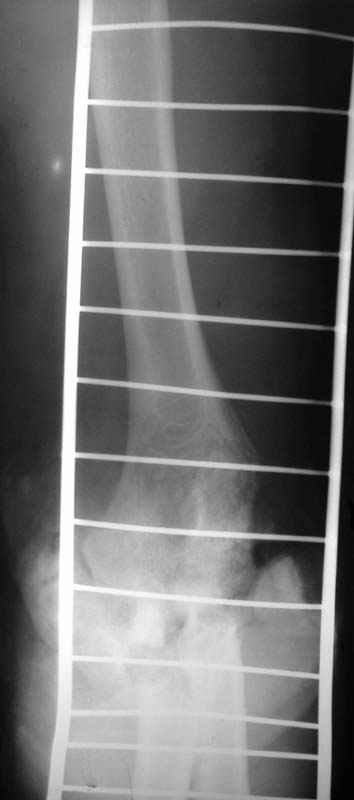

Операция - ПХО, ЧКО АВФ (см.приложение).

Репонировать фрагменты локтевой и плечевой кости не представилось возможным (по сути <каша> из мелких осколков сомнительной жизнеспособности), резекция головки лучевой кости, иссекли мягкие ткани, кожа зашита почти без натяжения, дренажи, АВФ.